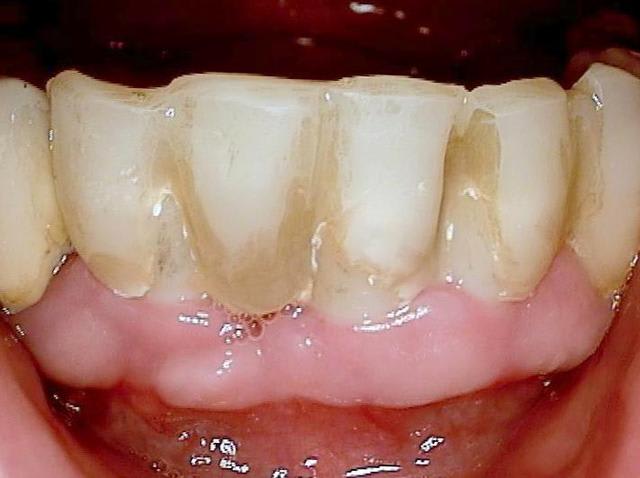

Sur la photo 14 (implants mandibulaires)

J'aime bien ce cas, sauf peut-être pour une certaine proximité des implants, car même si l'os peux être ok, pas facile pour la prothèse et son entretient.

ton commentaire m a fait remarqué que je n´ ai pas mis la photo de la prothèse du cas! merci ! :-)

ci dessous

Folie1 ofu0m9 - Eugenol

Folie2 z7edyr - Eugenol

Folie3 aeqhya - Eugenol

Folie4 q9egfx - Eugenol

Folie5 icxmia - Eugenol